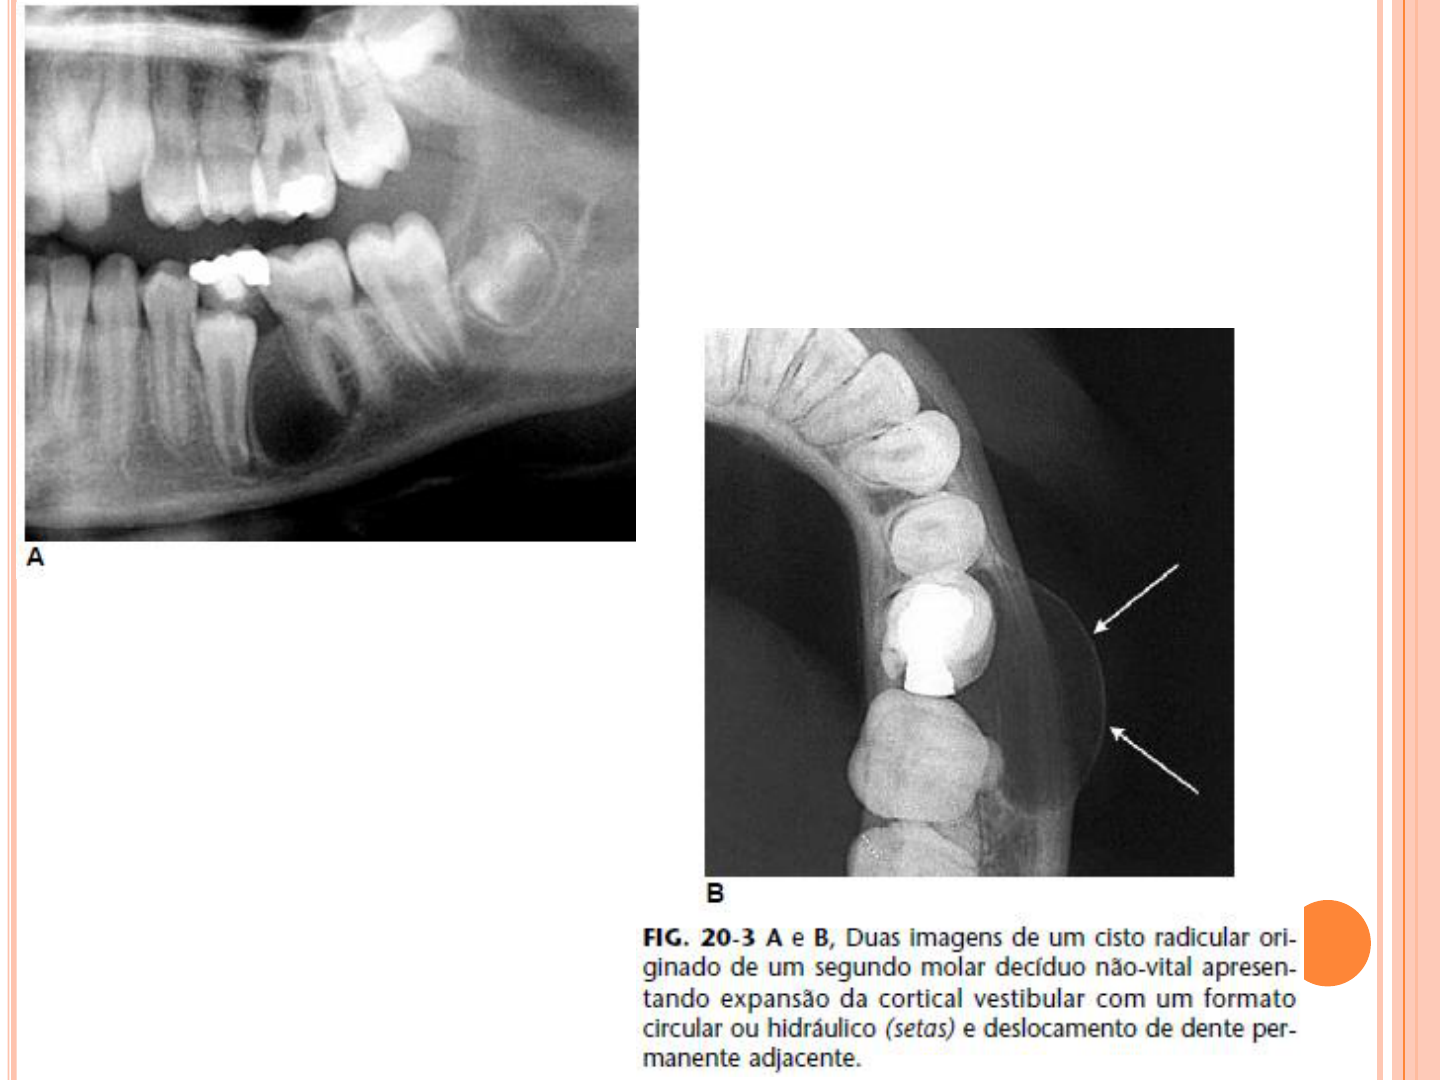

Osteomielitis Crónica Supurativa en Maxilar Superior: Informe de Caso - Studocu

image size: 1243x793